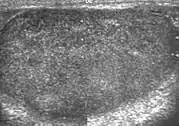

Patients with testicular lymphoma are usually old aged around 60 years of age, present with painless testicular enlargement and less commonly with other systemic symptoms such as weight loss, anorexia, fever and weakness. Bilateral testicle involvements are common and occur in 8.5% to 18% of cases. At sonography, most lymphomas are homogeneous and diffusely replace the testis [Fig. 7]. However focal hypoechoic lesions can occur, hemorrhage and necrosis are rare. At times, the sonographic appearance of lymphoma is indistinguishable from that of the germ cell tumors [Fig. 8], then the patient's age at presentation, symptoms, and medical history, as well as multiplicity and bilaterality of the lesions, are all important factors in making the appropriate diagnosis.